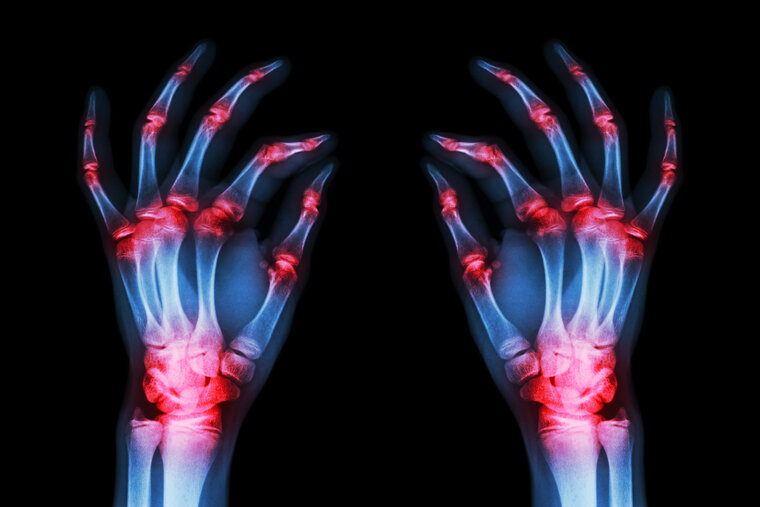

Rheumatoid arthritis (RA) is an autoimmune condition that causes pain and inflammation in the body’s joints. The immune system attacks the synovium (the lining of the joints), leading to inflammation, stiffness, swelling and pain that usually affect the hands, knees or ankles but can also cause issues with the eyes, heart, circulatory system and lungs.

Chronic inflammatory diseases are the most significant cause of death in the world, and the WHO ranks chronic diseases as the greatest threat to human health. RA is the most common chronic inflammatory joint disease and is a leading cause of disability globally. In 2019, 18 million people worldwide were living with the condition, suffering from mobility issues and physical weakness that impact their everyday lives and general well being. Untreated RA can lead to serious joint damage, complications in the major organs and a reduced life expectancy.